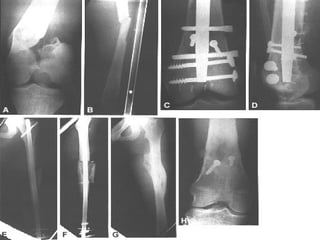

CLASIFICACION Las clasificaciones complementarias se basan en el grado de lesión de partes blandas, siendo la mas utilizada la de Gustilo

CLASIFICACION DE GUSTILLO I:  Herida < 1 cm. Herida limpia realizada por un fragmento puntiagudo de hueso que perfora la piel, existe escasa lesión a tejidos blandos, sin signos de aplastamiento, son por baja energía

CLASIFICACION DE GUSTILLO II:  Longitud > 1 cm. Sin colgajos, avulsiones y sin una gran lesión de tejido blando, existe un mínimo a moderado aplastamiento, conminución y contaminación moderada

CLASIFICACION DE GUSTILLO III:  Lesión extensa de tejidos blandos que afectan al músculo, piel y estructuras neurovasculares, suele existir un alto grado de contaminación, son por alta energía A)  cobertura adecuada de tejido blando del hueso, sin importar el tamaño de la herida

CLASIFICACION DE GUSTILLO B)  Afectación extensa o perdida del tejido blando con exposición del hueso, contaminación masiva y una grave fractura conminuta C)  Se asocia a lesión arterial  que necesita reparación independientemente del grado de lesión del tejido blando

CLASIFICACION Las clasificacionescomplementarias se basan en el grado de lesión de partes blandas, siendo la mas utilizada la de Gustilo

CLASIFICACION DE GUSTILLOI: Herida < 1 cm. Herida limpia realizada por un fragmento puntiagudo de hueso que perfora la piel, existe escasa lesión a tejidos blandos, sin signos de aplastamiento, son por baja energía

CLASIFICACION DE GUSTILLOII: Longitud > 1 cm. Sin colgajos, avulsiones y sin una gran lesión de tejido blando, existe un mínimo a moderado aplastamiento, conminución y contaminación moderada

CLASIFICACION DE GUSTILLOIII: Lesión extensa de tejidos blandos que afectan al músculo, piel y estructuras neurovasculares, suele existir un alto grado de contaminación, son por alta energía A) cobertura adecuada de tejido blando del hueso, sin importar el tamaño de la herida

CLASIFICACION DE GUSTILLOB) Afectación extensa o perdida del tejido blando con exposición del hueso, contaminación masiva y una grave fractura conminuta C) Se asocia a lesión arterial que necesita reparación independientemente del grado de lesión del tejido blando